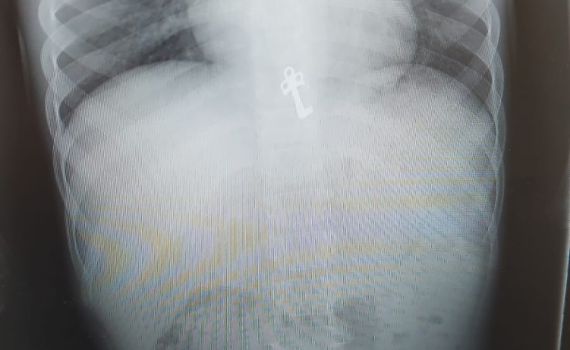

בצילום חזה, מצא רופא הילדים ד"ר חגי שטרן את המפתח הזעיר כשהוא בקיבתו של הילד. היותו של המפתח משונן ודוקרני חייב פעילות פולשנית של הוצאת המפתח מחשש לסיכון ולקרע במעבר למעי, ובשל כך הועבר הילד לחדר ניתוח בבית החולים.